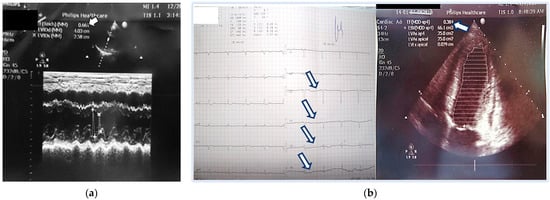

| third day | 1. acute left side heart failure symptoms—cardiac asthma 2. marked reduction EF = 30% 3. treatment as in heart failure with reduced EF—torasemide 5 mg, carvedilol 2 × 3.125 mg, ramipril 2.5 mg, aspirin 100 mg |

| first month | 1. no cardiac sighs 2. EchoC-normal EF, but persist regional apical wall motion abnormalitica 3. coronary angiography—normal 4. Initially diagnosis—perypartal cardiomyopathy 5. treatment with torasemide 5 mg, carvedilol 2 × 3.125 mg, and ramipril 2.5 mg |